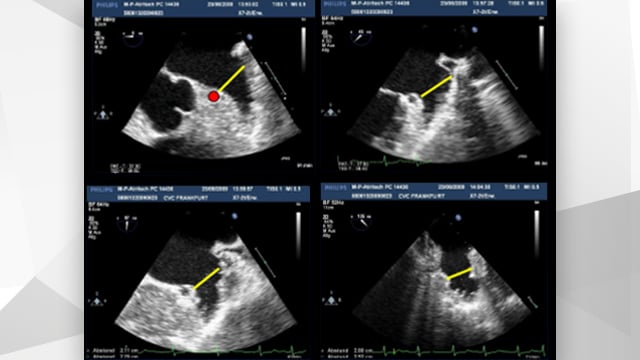

This PCR Textbook chapter reviews the underlying concepts involving atrial fibrillation, outlines anticoagulation strategies for thromboembolism prevention, and describes the current state and future directions of left atrial appendage occlusion.